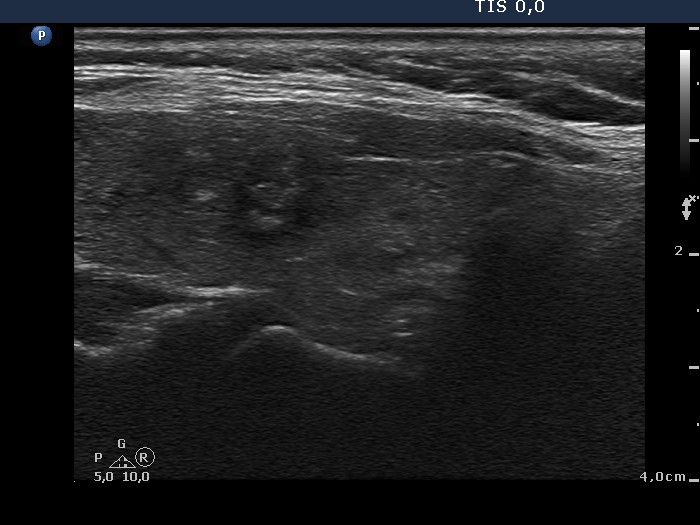

Benign hyperplastic nodule (histological diagnosis) - case 80 |

Papillary carcinoma (histological diagnosis) - case p057 |

The two cases differ in the lack and presence of punctate echogenic foci, benign (left) and malignant (right) case, respectively.